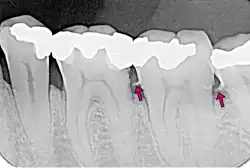

- le tartre supra-gingival : c'est celui qu'on peut voir à l'œil nu. Il est généralement de couleur blanchâtre ;

- le tartre sous-gingival : c'est le tartre qui s'est déposé sur la racine de la dent, à l'abri de la gencive, au niveau des poches parodontales. Il est souvent beaucoup plus foncé. Ce tartre est le plus dommageable : les bactéries sont protégées à l'intérieur de la poche, et progressivement la flore aérobie se transforme en flore anaérobie, plus pathogène. Par ailleurs, comme on ne le voit pas, on ne s'en rend pas compte.